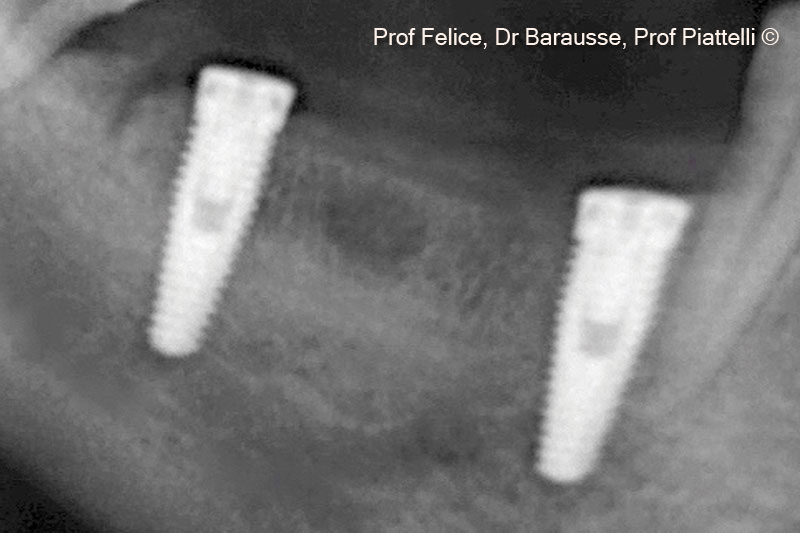

Một bệnh nhân nữ (70 tuổi) có biểu hiện teo xương hàm dưới bên phải phía sau.

Vật liệu sinh học đã qua sử dụng

Sp-block